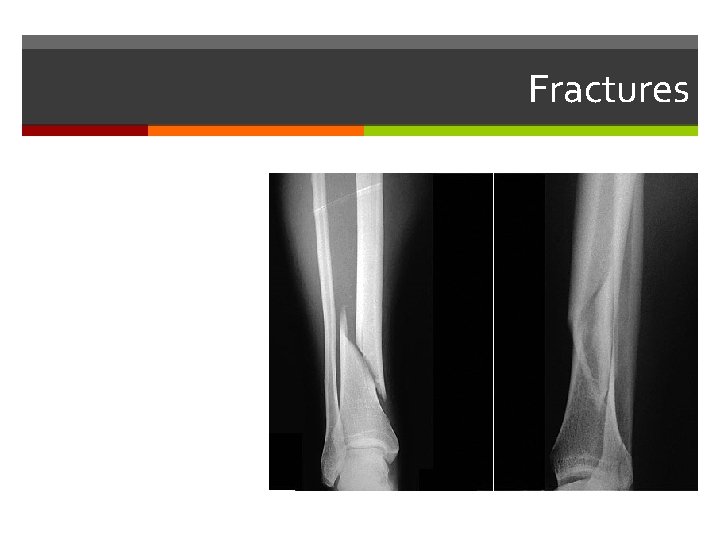

Fractures

Fractures Treated by Reduction: Closed Open